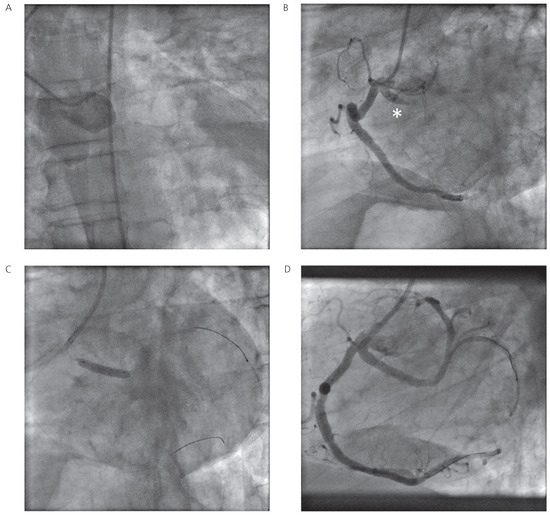

Myocardial Infarction in a Patient with a Single Coronary Artery